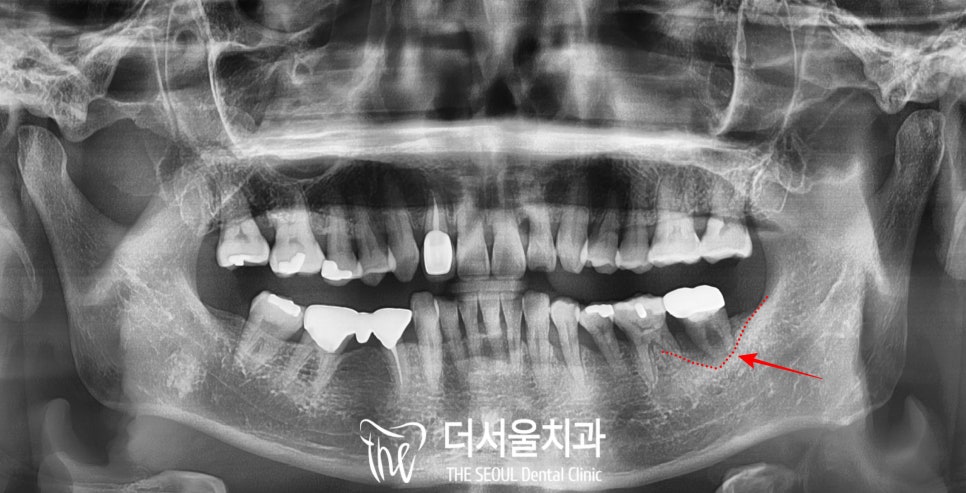

모란역 치과 에 온 환자의

파노라마를 먼저 보겠습니다.

왼쪽 아래 두 번째 큰 어금니의

까만 골소실 부위가 보이실까요?

이분은 치주 질환으로 인하여

평소 스케일링과 검진이

반드시 필요하셨던 분인데,

직장이 바쁘기도 하고

내원하기가 조금은 귀찮으시다는 이유로

임의로 방문을 중단하셨습니다.

그리고 꽤 오랜 기간 검진을 받지 않다가

어금니에 동요도가 생겨 병원을 가보니

발치 후 임플란트 소견을

들으셨다고 하시네요.